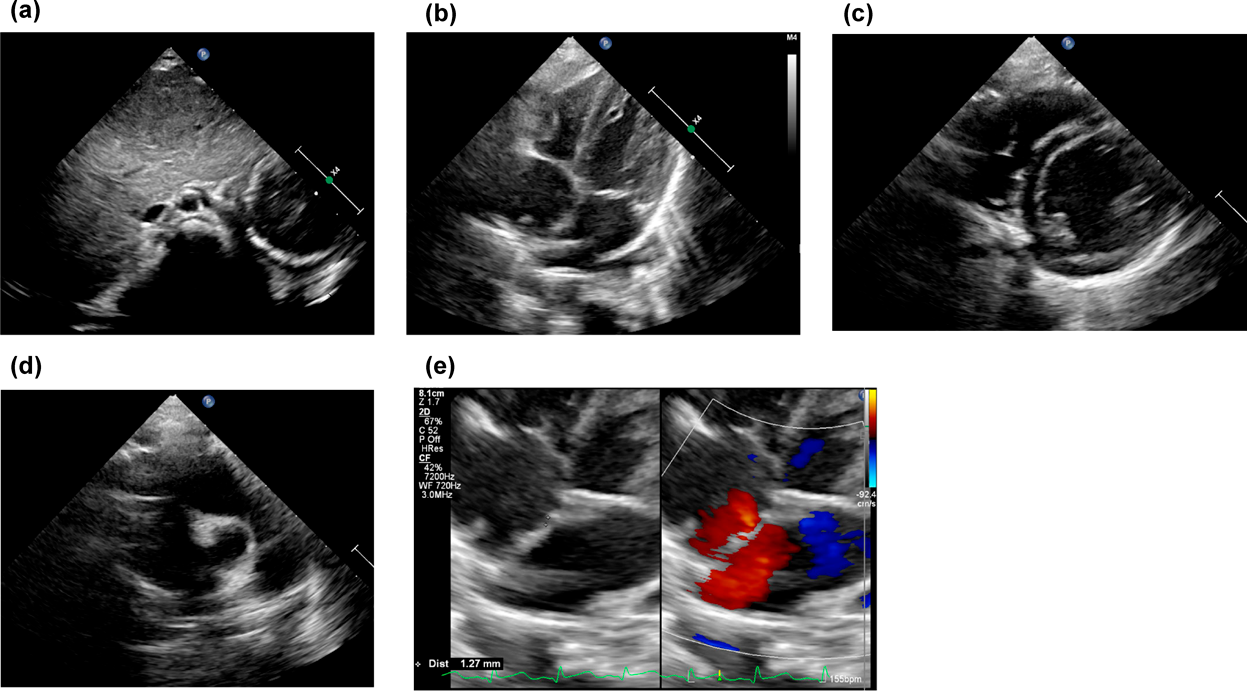

採血では白血球21,900/µL,CRP 0.32 mg/dLと軽度の炎症反応上昇を認めた(Table 1).単純胸部X線ではCTR 42%,含気の左右差と右下肺野に無気肺を認めたが明らかな肺炎像はなかった.また,胃泡は左側,肝臓は右側に認めた(Fig. 1a).心電図所見は正常洞調律でP,QRS波形は一種類のみであった(Fig. 1b).心エコー検査では心房位はsolitus,心室位D-loop,大血管位D-spiralであった.1.2 mmの心房中隔欠損による左右短絡を認め,右側大動脈弓であったが,房室弁や肺静脈還流に異常は認めなかった(Fig. 2a–f).

Fig. 2 (a)–(d) Echocardiography of the depicts situs solitus, D-loop, and D-spiral. (e) There was a left-to-right shunt due to a 1.2-mm atrial septal defect

入院後,気道感染に伴う気管支喘息の増悪としてステロイドの全身投与,吸入による治療を開始した.しかし喘息としてはステロイド,β刺激薬に対する治療への反応に乏しく入院2日目に中止した.入院3日目に喘鳴の増悪を認め,High-flow nasal cannula(HFNC)を導入した.吸気性喘鳴の鑑別のため耳鼻科でファイバー検査を施行したが喉頭軟化症を含め上気道狭窄病変は認めなかった.入院5日目に再度発熱したため採血を再検したところWBC 24200/µL,CRP 1.4 mg/dLと炎症反応の上昇を認め,ABPC/SBT(134 mg/kg/day)の投与を開始した.鼻腔から喉頭までの気道狭窄病変を認めないにもかかわらず,喘鳴が持続したため下気道評価の目的に造影CTを行うこととした.また,事前に鎖肛治療のために受診していた病院の画像・情報提供を取り寄せたところ無脾症候群の疑いがあることが判明したため,腹部も撮影する方針とした.入院9日目に行った造影CTでは心臓・大血管については右大動脈弓であり,左鎖骨下動脈起始異常を伴っていた.水平断では左鎖骨下動脈は気管の後ろを走行していたが気管の圧排・変形は認めなかった.血管走行の異常は認めたが,気管を圧排する所見がなかったことから,血管輪,vascular slingによる喘鳴は否定的と判断した.肺静脈還流異常も含め複雑心疾患は認めず,心耳形態は正常であった(Fig. 3a–e).肺については,右肺は三葉,左肺は二葉で肺葉に相同性はなかった.気管については,右上葉気管支が気管分岐部よりも上部から分岐しており気管気管支の形態であった.気管気管支に加えて右中葉・下葉に向かう気管支が正中をまたいで左から右に遊走する気管走行をしておりbridging bronchusであった.右上葉気管気管支が分枝するレベルで狭窄を認めており喘鳴の原因と考えられた.腹部所見では胆嚢は描出されたが,脾臓は同定できなかった(Fig. 4a, b).後日再検した血液像でHowell Jolly小体を1%認め,複雑心疾患を伴わない無脾症候群と診断した.喘鳴は徐々に改善し,入院9日目にはHFNCから離脱し,入院11日目に退院となった.以降,かかりつけ病院で抗菌薬の予防内服が開始された.